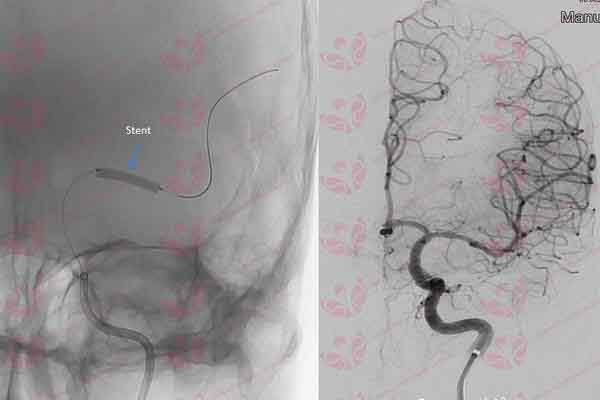

Một bệnh nhân 57 tuổi được chẩn đoán nhồi máu não và được điều trị tiêu sợi huyết nhưng không thuyên giảm. Sau đó, bệnh nhân được ứng dụng phần mềm trí tuệ nhân tạo Rapid để đánh giá và can thiệp chính xác lấy huyết khối động mạch não do tắc hoàn toàn động mạch não trái, cứu sống thành công bệnh nhân.